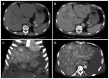

Peliosis hepatis (PH) is a vascular lesion of the liver that mimics a hepatic tumor. PH is often associated with underlying conditions, such as chronic infection and tumor malignancies, or with the use of anabolic steroids, immunosuppressive drugs, and oral contraceptives. Most patients with PH are asymptomatic, but some present with abdominal distension and pain. In some cases, PH may induce intraperitoneal hemorrhage and portal hypertension. This study analyzed a 46-year-old male who received a transplanted kidney nine years prior and had undergone long-term immunosuppressive therapy following the renal transplantation. The patient experienced progressive abdominal distention and pain in the six months prior to this study. Initially, imaging studies revealed multiple liver tumor-like abnormalities, which were determined to be PH by pathological analysis. Because the hepatic lesions were progressively enlarged, the patient suffered from complications related to portal hypertension, such as intense ascites and esophageal varices bleeding. Although the patient was scheduled to undergo liver transplantation, he suffered hepatic failure and died prior to availability of a donor organ.